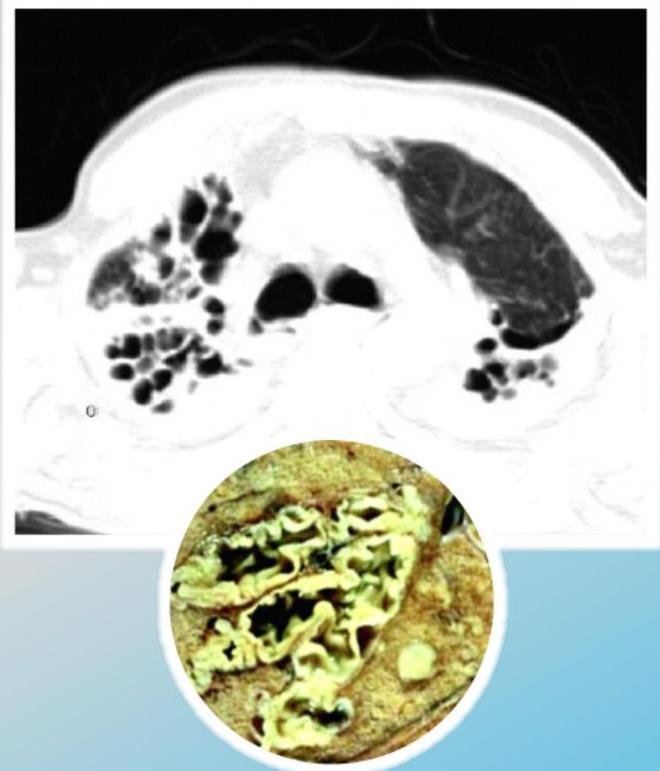

- ☐ Thin-section HRCT scanning: is the gold standard, with excellent sensitivity and specificity.

- ☐ Chest X-ray: increase in size and loss of bronchovascular markings, crowding of bronchi, and loss of lung volume. Severe case: Honeycombing.

Radiographic Findings (Chest X-ray)

Conglomerating cysts of varying size and wall thickness. “Honeycomb” sign.

Radiographic Findings (Signs)

Bronchial wall thickening and widening with parallel configuration. Tram track sign.

CT Scan Findings

Cylindrical

Saccular/Varicoid

Cystic

Signet Ring Appearance

CT scan showing bronchiectasis. Note the dilated bronchi with thickened wall, which are larger than adjacent arteries, giving a signet ring appearance.